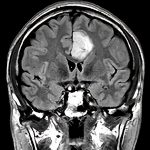

左後頭頂葉腫瘤

頭蓋内腫瘍摘出術

No.’21_62 手術前1

No.’21_62 手術前2